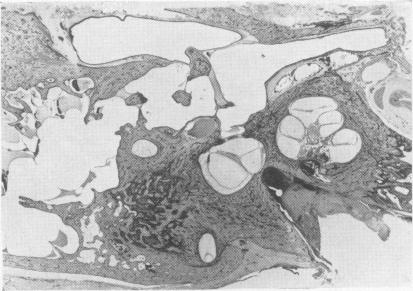

Ménière's disease.

Postgrad Med J. 1955 Jul;31(357):330-40. doi: 10.1136/pgmj.31.357.330.